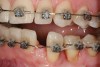

Figure 9  Orthodontic distraction osteogenesis to develop the implant site of tooth No. 23.

Figure 9